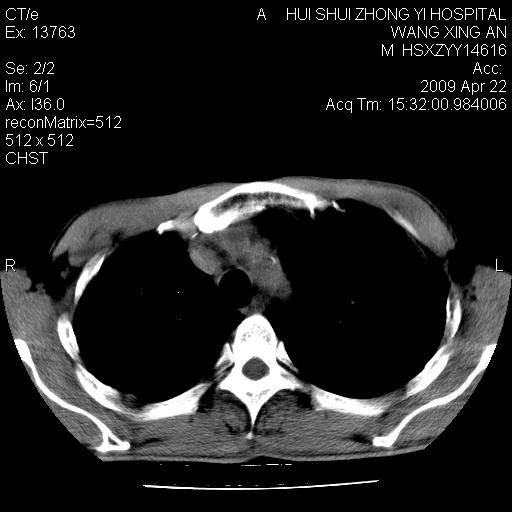

标题: CT19534:患者男、46岁咳嗽、胸痛半月。 [打印本页]

标题: CT19534:患者男、46岁咳嗽、胸痛半月。

1、右下肺中央型肺癌并右肺转移,右肺下叶不张。(肿块围绕右肺下叶支气管生长,致管腔闭塞右肺下叶不张;右肺有结节影)。

2、右侧胸腔积液。

3、右中上肺陈旧性肺结核(右肺见纤维化病灶及点状钙化)。

1、右下肺中央型肺癌并右肺转移,右肺中下叶不张。(右肺有结节影)。胸骨转移

2、右中上肺陈旧性肺结核(因为大多为纤维灶)。

3、右侧胸腔积液。

1)右肺中间段支气管癌并右肺下叶肺不张。2)右肺上叶、两肺下叶背段感染性病变。3)右侧少量胸腔积液。